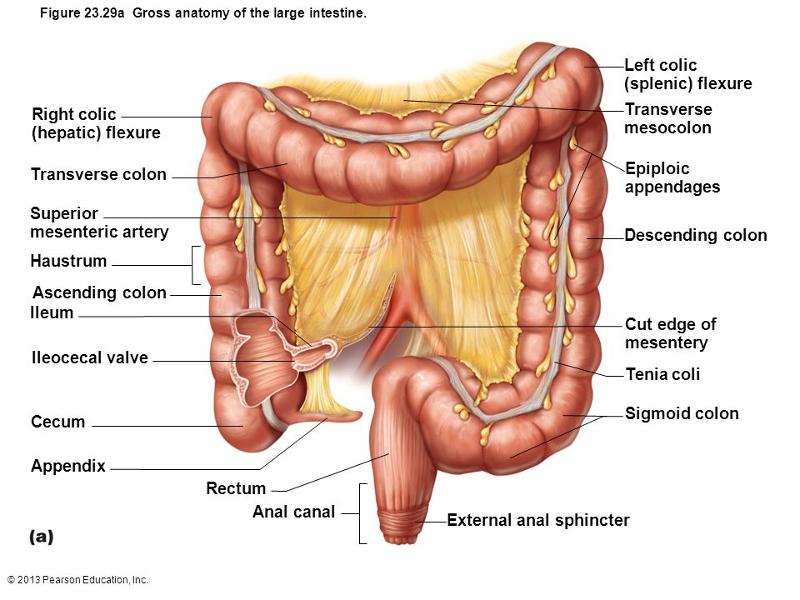

The Small and Large Intestines

Colorectal Surgery